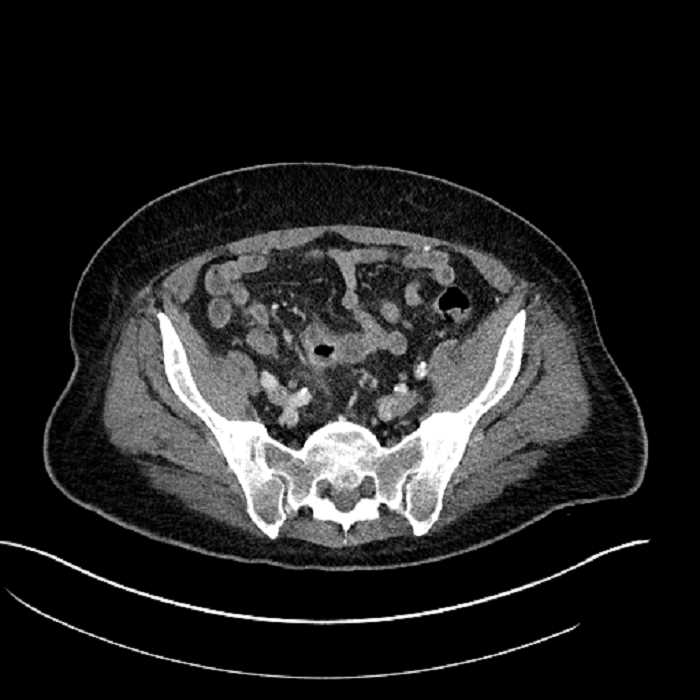

• Mild mural thickening of a segment of the sigmoid colon with adjacent fat stranding and a 1.5 cm fluid and gas collection along the tip of an inflamed diverticulum

• Loss of the normal fat plane between this collection and adjacent loops of small bowel, which demonstrate mural thickening

• No bowel obstruction

• High grade stenosis of the left common iliac artery, with the left internal and external iliac arteries remaining patent

Acute sigmoid diverticulitis complicated by a small contained perforation and a large abscess in the right hepatic lobe. Additional small subcapsular abscesses along the anterior margin of the left hepatic lobe.

Additionally, loss of the normal fat plane between the peridiverticular collection and adjacent thickened loops of small bowel raises the potential for an enterocolonic fistula.

Hepatic abscess showing the double target sign with low density internally surrounded by a thin inner enhancing rim (red arrow) and ill-defined outer low density rim (yellow arrow). Blue arrow indicates an internal septation. Red arrows: additional smaller subcapsular abscesses. Red arrow: focal contained perforation associated with diverticulitis.